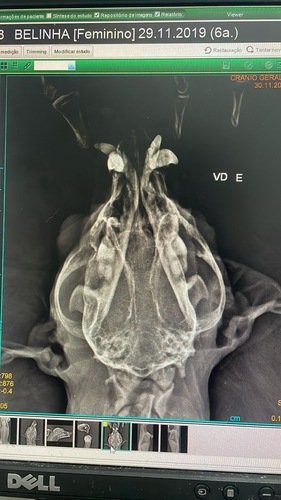

Eu morro de medo de fogos e ontem, por conta do jogo, eu pulei da sacada de casa e estou cheia de machucados - o pior deles é a fratura da mandíbula!!

Estou internada e sendo medicada, porque isso dói muito! Fiz todos os exames e estou me comportando muito bem, mas os tios veterinários falaram que precisarei de cirurgia!